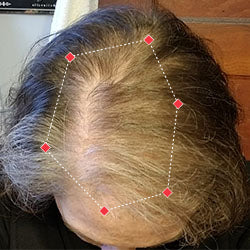

Indications for Use

The iRESTORE Hair Growth System Elite is indicated to promote hair growth in males who have Norwood-Hamilton Classifications of IIa to V and in females who have Ludwig-Savin Classifications I to II, and in both with Fitzpatrick Skin Phototypes I to IV. In other words, iRESTORE is not intended for people who are bald or have advanced hair loss.

Read more in our user manual for Indications of Use, Contraindications, Warnings, and Precautions to find out if iRESTORE is suitable for you.

Laser therapy works to reactivate thinning and dormant hairs. For completely bald areas of the scalp, there may be no way to promote hair regrowth. If you still have hair follicles, laser therapy may be beneficial to you.

Not sure? Email us to have our specialists evaluate your scalp conditions to see if iRESTORE is suitable for you.